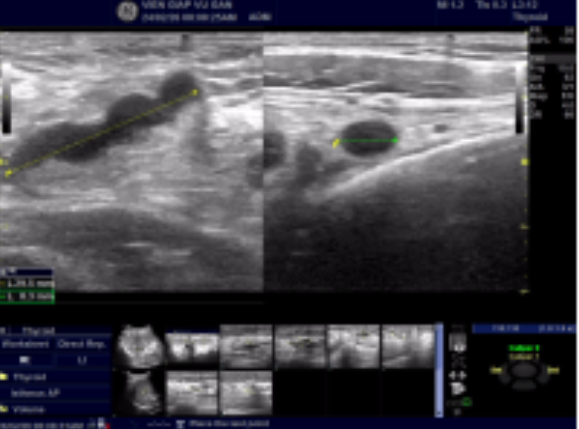

Đánh giá hạch vùng

- Hạch nách nhóm I, II: 10–25mm, mất rốn hạch

- Hạch Rotter: 6mm, mất rốn hạch. Điều này cho thấy khả năng di căn hạch (N1–N2). Khi đã có di căn hạch, Cá thể hóa điều trị ung thư vú càng trở nên quan trọng để lựa chọn phác đồ toàn thân phù hợp.